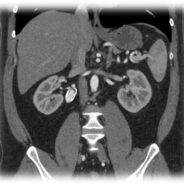

Pár kép az oktatás radiológiai részéről:

(SE-OKK, SIEMENS, CTISUS)